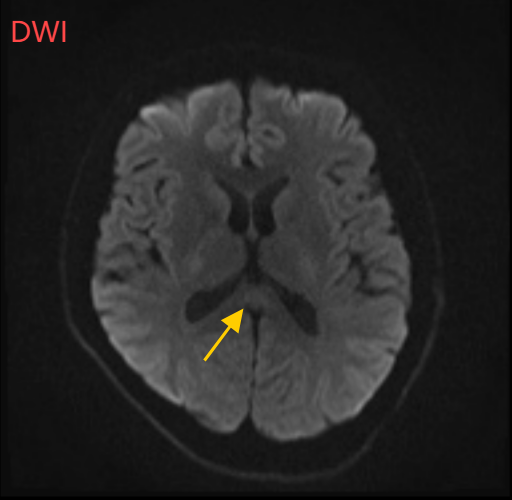

图片

经过一周治疗,小董的胼胝体压部病变明显好转